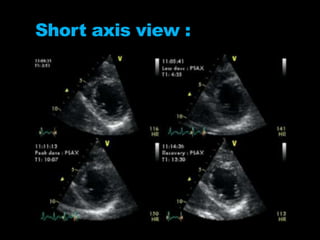

Short axis view :